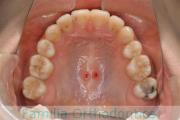

No.22V-296

- 叢生

- 上顎前突

- 19歳

- 女性

- 844

- 8448

- FEA

- 88万円

上の出っ歯を治したいとのことで来院されました。下あごの後退が強く、奥歯のすれ違いもありました。上顎のみ左右小臼歯を、親知らずは全て抜歯して、マルチブラケット法を行いました。2年半、30回程度の通院が必要でした。

上野前歯の移動量が大きく、この部位の歯根吸収のリスクが高いケースでした。